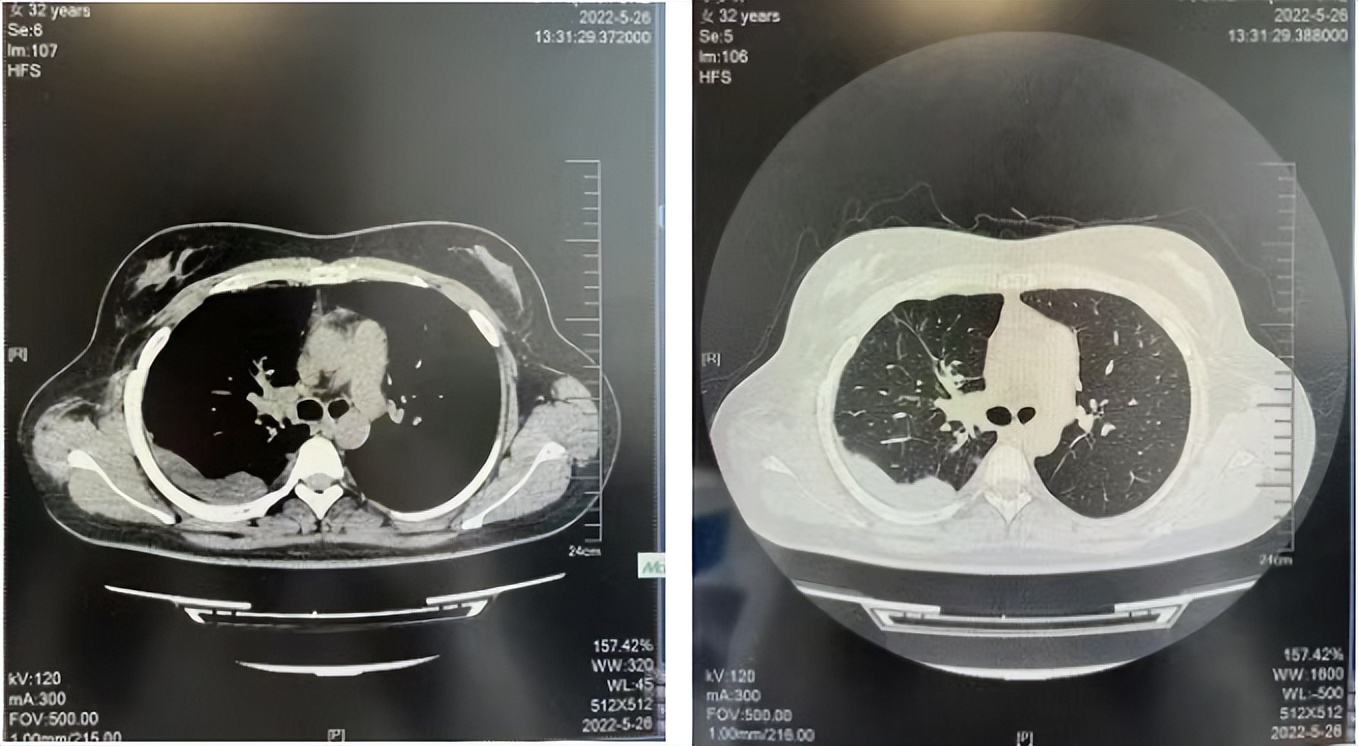

2016年1月复查CT提示支气管截断可见新发小结节,一线治疗采用培美曲塞+DDP方案化疗4周期(培美曲塞3.36,DDP 480mg)。化疗后复查胸部CT:右肺见不规则结节样影,最大层面大小约19mm*8mm,较前比较明显增大,疗效评估PD。2017.3-2017.4予单药多西他赛化疗3周期,疗效评估SD。2018年5月末复查CT提示结节较前增大,评效为PD,2018年6-10月予多西他赛+CBP化疗4周期,疗效评估SD。2022年5月患者出现活动后气短,复查胸部CT示右肺膨胀不良;右侧胸腔积液增多。胸腔积液包埋病理示符合肺腺癌细胞。行NGS基因检测:EML4:exon13-ALK:exon20融合。PD-L1(克隆号22C3)TPS<1%。

2022.05

2022.08

2023.05

2024.12